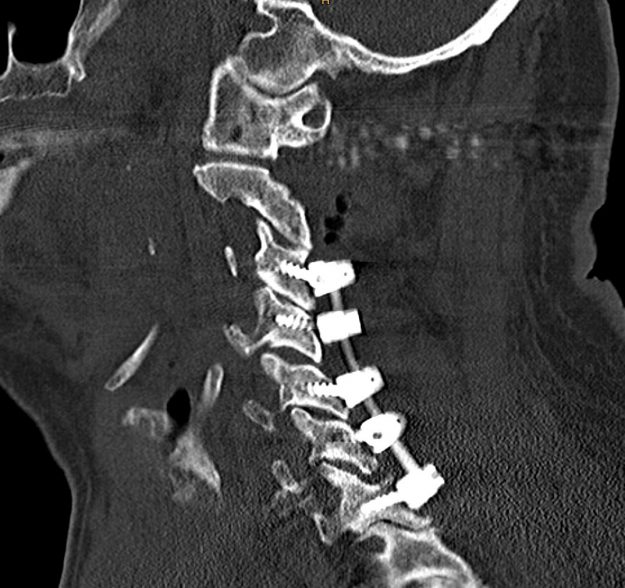

Μετάσταση 10ου Θωρακικού Σπονδύλου (Θ10)

Ασθενής άνδρας 72 ετών με έντονη ραχιαλγία και ιστορικό καρκίνου του πνεύμονα. Ο απεικονιστικός έλεγχος με μαγνητική και αξονική τομογραφία της σπονδυλικής στήλης ανέδειξε μάζα κυρίως στο σώμα του 10ου θωρακικού σπονδύλου (Θ10) με περιβρογχισμό και πίεση επί του νωτιαίου μυελού. (Σημειώστε και τη διήθηση του Θ9 σπονδύλου, χωρίς οστεόλυση). Διενεργήθη αποσυμπίεση του νωτιαίου μυελού…